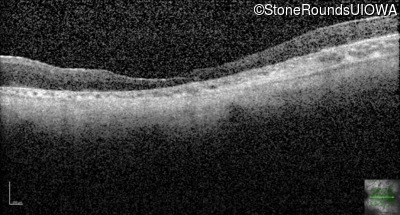

Age at visit: 28 years

Age at visit: 29 years